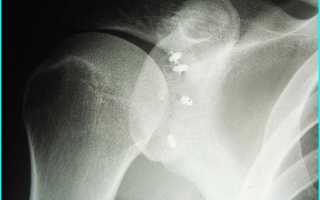

Артроскопический шов надостной мышцы выполняется с использованием рассасывающихся или титановыми якорями. На рисунке представлена послеоперационная рентгенограмма с титановым якорем и вариантами фиксаторов.